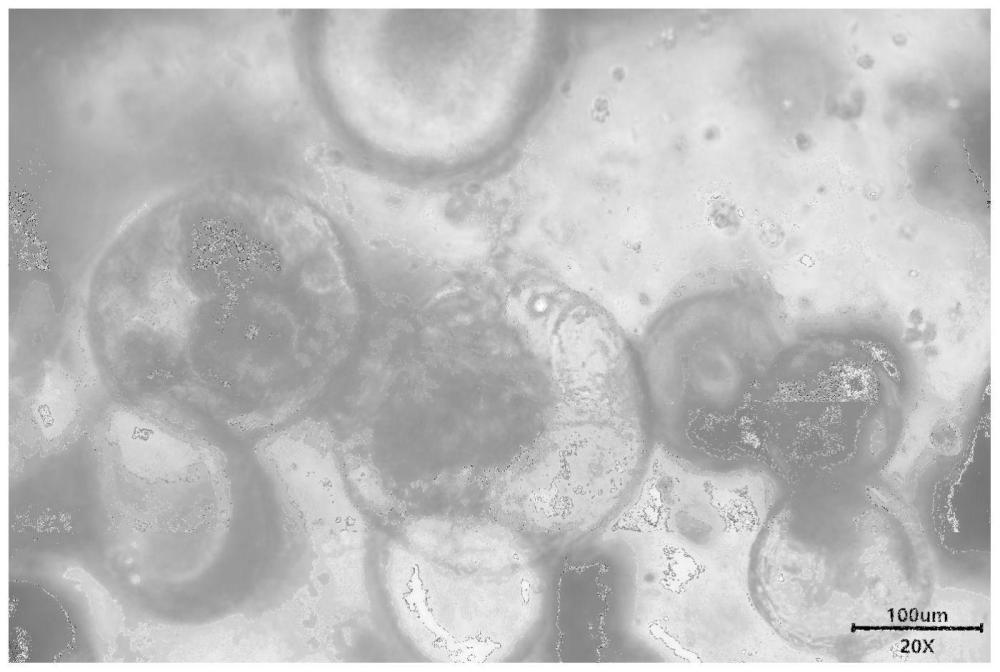

| 摘要: | 一种人胆管胆囊细胞3D培养的培养基与培养方法,培养基由基础培养基和特异性添加因子组成,特异性添加因子中Wnt3A 10~500ng/ml,R‑spondin50~5000ng/ml。培养方法为:(1)将人源的肝组织、胆囊组织或胆管组织预处理,切成组织块;(2)消化和过滤;离心去除上清液;(3)采用人胆管胆囊细胞3D培养的培养基进行重悬,冰上取基质胶与细胞悬液混合;(4)滴到培养皿中;(5)培养箱内静置后倒扣,胶滴凝固后静置;(6)加人胆管胆囊细胞3D培养的培养基,培养箱培养;(7)定期更换培养基,培养3~5天获得类器官。本发明可根据不同应用目的进行多种培养操作,简化了培养操作,并使得培养结果具有较高的稳定性。 | ||||